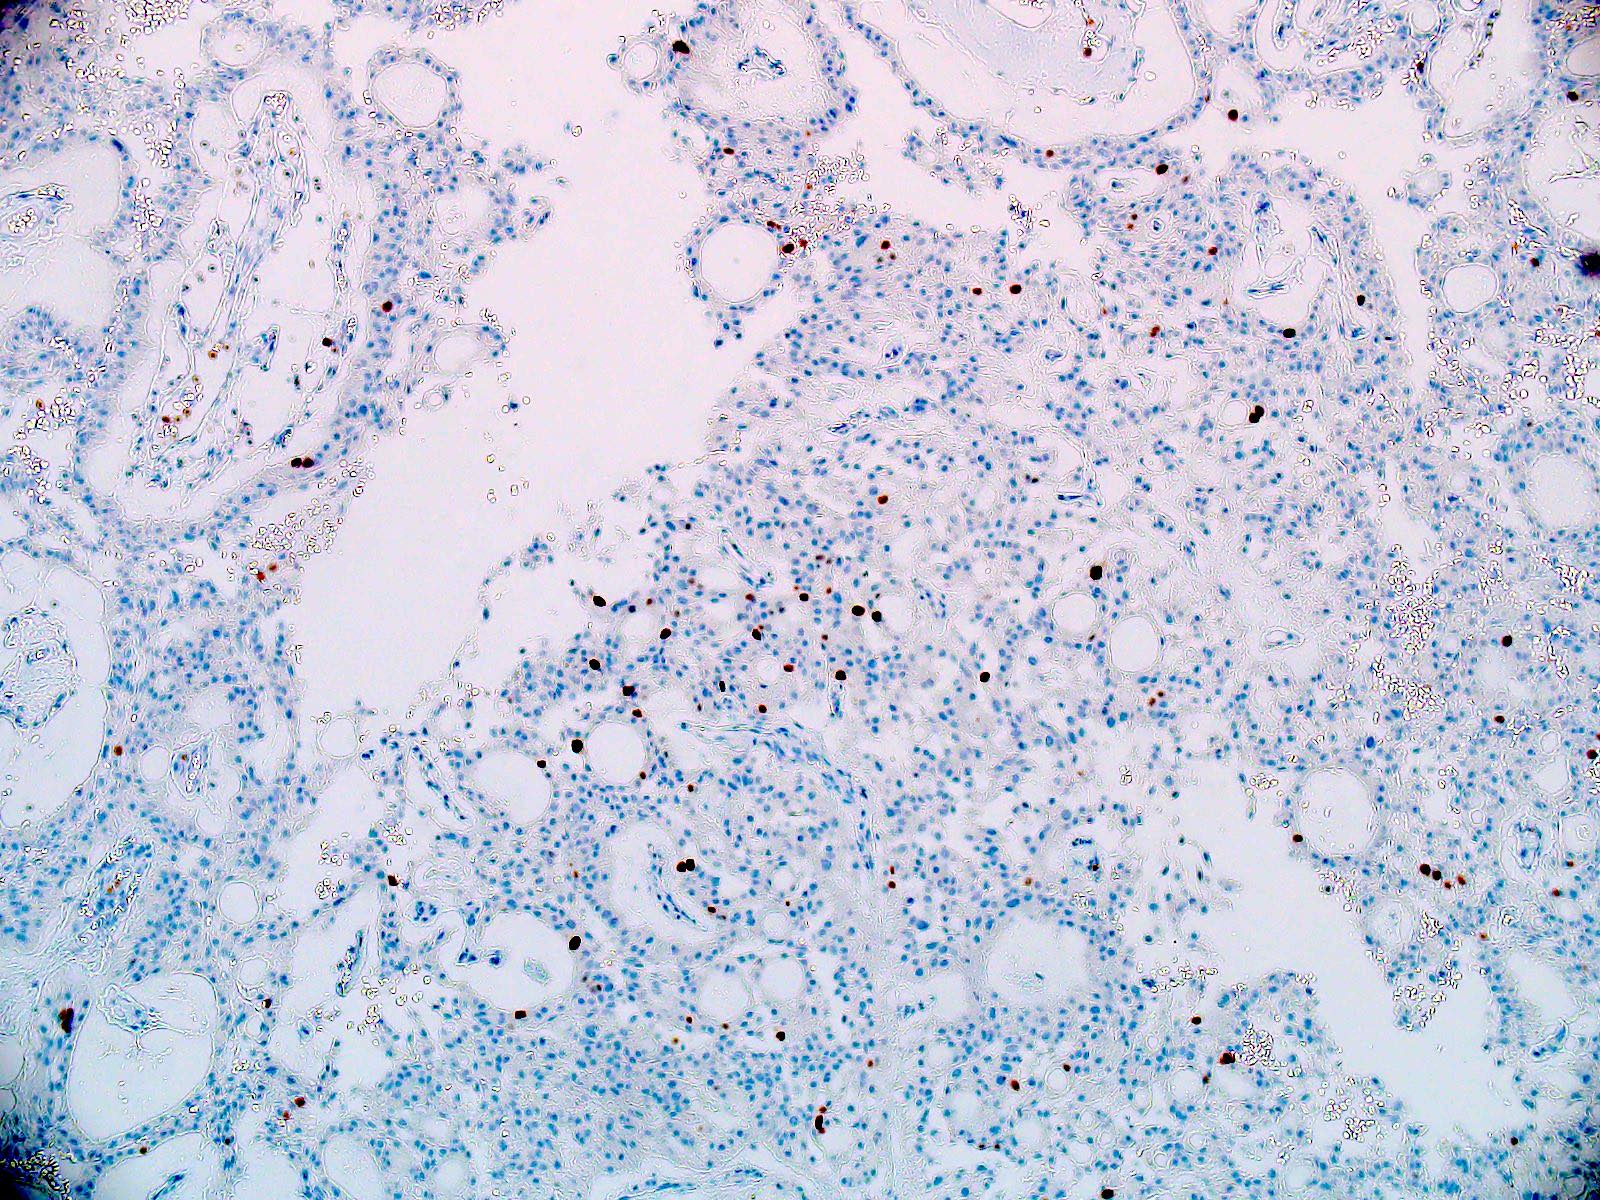

Microscopic (histologic) description

- Most common pattern is radial arrangement of cuboidal to epithelioid elongated glial tumor cells around hyalinized fibrovascular (central, often hyalinized blood vessels) cores in a papillary configuration

- Accumulation of basophilic myxoid material around blood vessels (myxoid stroma) and in microcysts

- Myxoid material is highlighted by PAS and Alcian blue positive staining

- In cases composed of confluent sheets of epithelioid cells with little or no papillary structures, PAS and Alcian blue positivity is useful in reaching a correct diagnosis

- Fascicular growth and spindle cells are common

Microscopic (histologic) images

Positive stains

- Positive for GFAP (diffuse expression of GFAP distinguishes myxopapillary ependymomas from other tumors in the differential diagnosis, such as metastatic carcinomas, chordomas, paragangliomas, myxoid chondrosarcomas, schwannomas, etc.)

- Positivity for S100 is typical; CD99, vimentin and CD56 positivity is seen frequently

Negative stains

- Olig2 (tumor nuclei are negative), EMA (dot-like cytokeratin expression seen in other ependymoma variants is often absent)